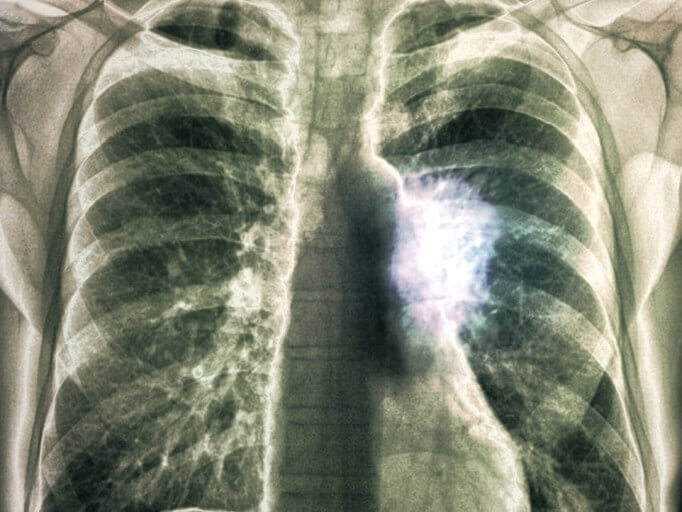

폐렴 치료

1) 일반적으로는 세균이라면 항생제, 바이러스라면 그에 알맞은 항바이러스제 투여를 하기도 합니다.

2) 결핵으로 인한 폐렴에는 항결핵제를 처방합니다. 증상에 따라서 해열제, 진통제 등 추가적인 처방을 내립니다.

3) 약 10-14일 정도의 폐렴 치료 기간이 필요합니다 증세를 관찰 후 추가적인 치료를 선택합니다.